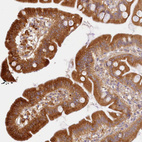

Immunohistochemical staining of human endometrium shows strong cytoplasmic positivity in glandular cells.